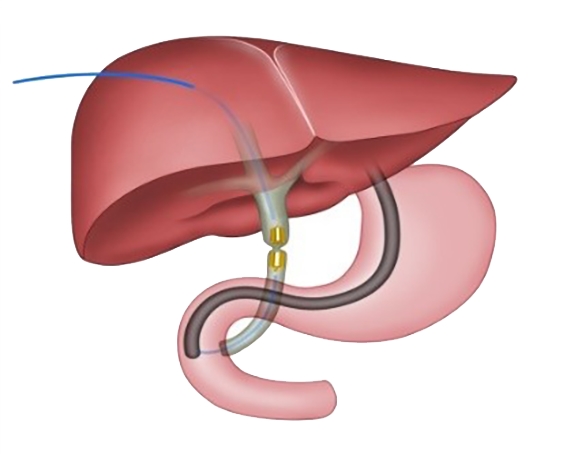

2025, 34(8):1783-1789. doi: 10.7659/j.issn.1005-6947.250076

摘要:背景与目的 肝内胆管癌(ICC)是一种起病隐匿、预后极差、初诊多为进展期的原发性肝癌,其治疗选择有限,预后差。本研究旨在探讨靶向治疗、免疫治疗与肝动脉灌注化疗(HAIC)联合应用于晚期ICC的转化治疗的潜力,为临床转化治疗提供参考。方法 回顾广东医科大学附属医院2021年11月收治的1例晚期ICC行靶向治疗、免疫治疗与HAIC联合治疗后成功转化并接受手术患者的诊治过程,并复习国内外相关文献。结果 患者为52岁男性,确诊为T2N1M0-Ⅲb期ICC。患者拒绝接受以吉西他滨联合顺铂为主的一线化疗方案,同意行靶向治疗联合免疫治疗与HAIC的综合治疗,在接受4个治疗周期后评估肿瘤达到部分缓解,具备实施根治性手术治疗的条件。患者随后接受了腹腔镜下肝S6段和部分S7段切除、胆囊切除以及肝门部和腹膜后淋巴结清扫术。术后患者规律行靶向免疫联合化疗的综合治疗方案。在疾病出现复发和转移后,化疗药物进行了相应调整。截至目前,患者无病生存期达15个月,总生存期超过3年。结论 靶向治疗、免疫治疗与HAIC三联方案可提高晚期ICC患者的转化机会并延长生存期,具有较好的安全性和临床应用前景,但其疗效仍需多中心研究进一步验证。